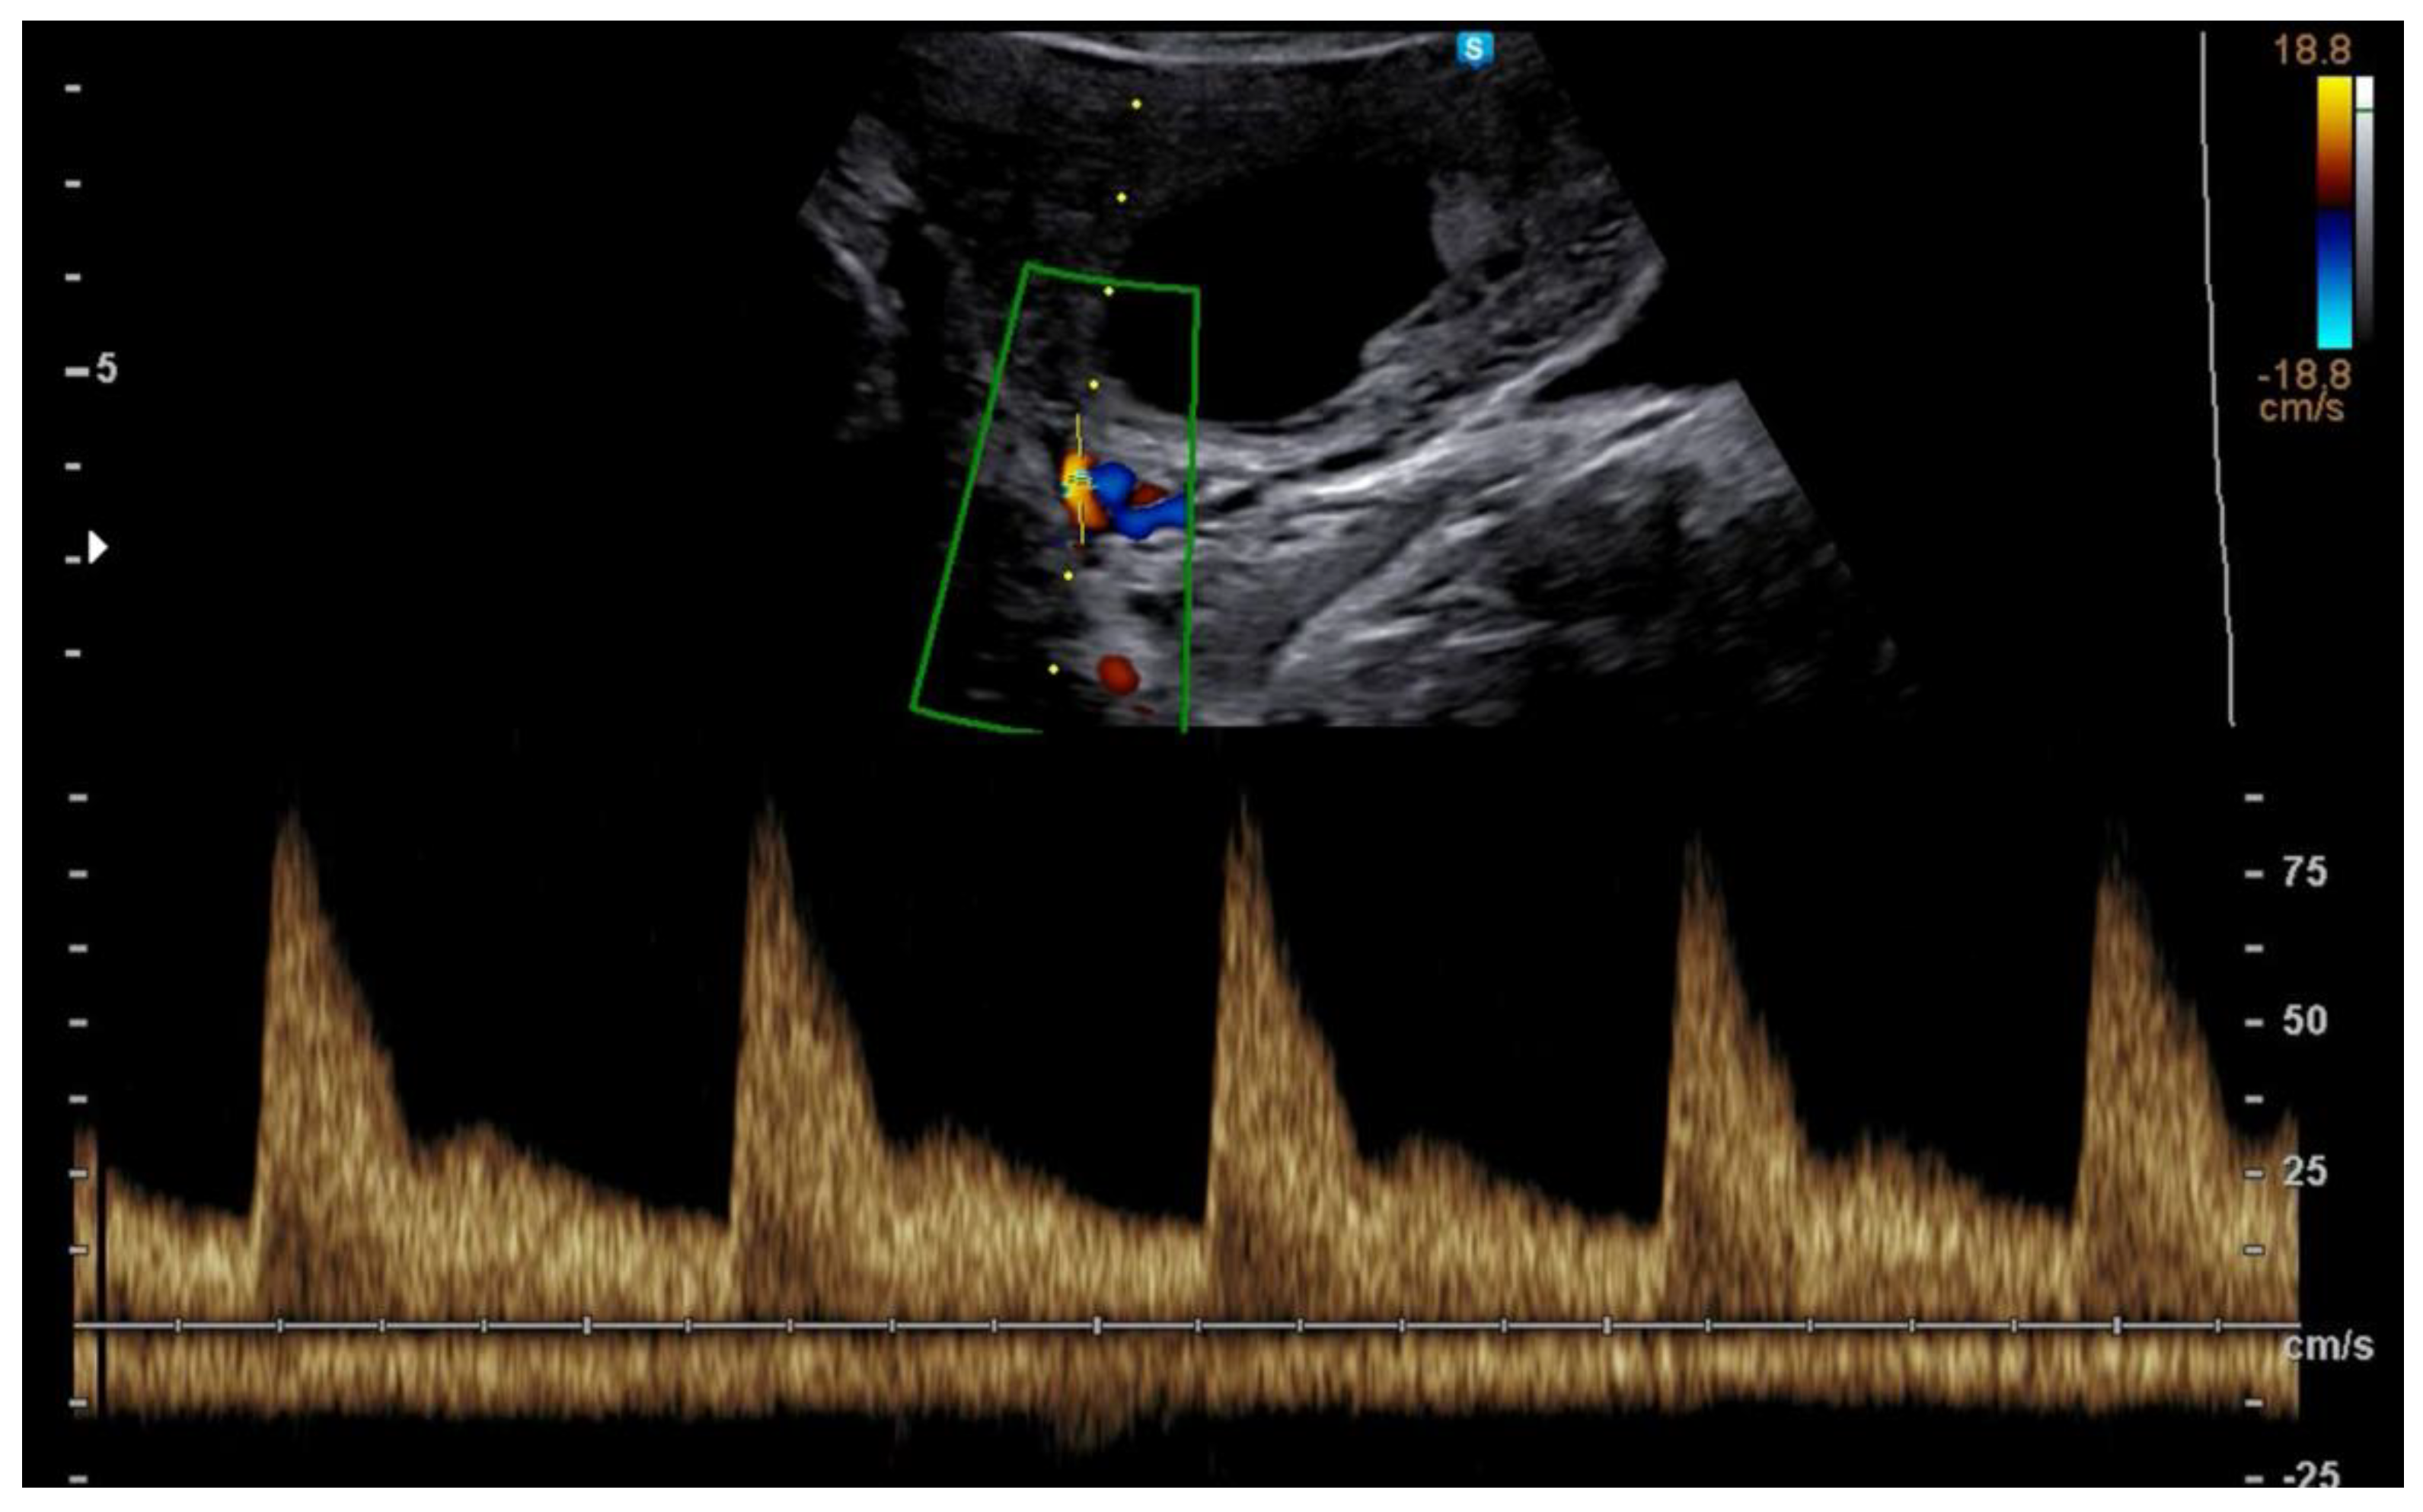

3.1. First Trimester Uterine Doppler

- Plasencia, W.; Maiz, N.; Bonino, S.; Kaihura, C.; Nicolaides, K. Uterine artery Doppler at 11+0 to 13+6 weeks in the prediction of pre-eclampsia. Ultrasound Obstet. Gynecol. 2007, 30, 742–749. [Google Scholar] [CrossRef]

- Velauthar, L.; Plana, M.N.; Kalidindi, M.; Zamora, J.; Thilaganathan, B.; Illanes, S.E.; Khan, K.S.; Aquilina, J.; Thangaratinam, S. First-trimester uterine artery Doppler and adverse pregnancy outcome: A meta-analysis involving 55974 women. Ultrasound Obstet. Gynecol. 2014, 43, 500–507. [Google Scholar] [CrossRef] [PubMed]

- Rizzo, G.; Capponi, A.; Cavicchioni, O.; Vendola, M.; Arduini, D. First trimester uterine Doppler and three-dimensional ultrasound placental volume calculation in predicting preeclampsia. Eur. J. Obstet. Gynecol. Reprod. Biol. 2008, 138, 147–151. [Google Scholar]

- Carbone, I.F.; Cruz, J.J.; Sarquis, R.; Akolekar, R.; Nicolaides, K.H. Assisted conception and placental perfusion assessed by uterine artery Doppler at 11–13 weeks’ gestation. Hum. Reprod. 2011, 26, 1659–1664. [Google Scholar]

- Prefumo, F.; Fratelli, N.; Soares, S.C.; Thilaganathan, B. Uterine artery Doppler velocimetry at 11–14 weeks in singleton pregnancies conceived by assisted reproductive technology. Ultrasound Obstet. Gynecol. 2007, 29, 141–145. [Google Scholar] [CrossRef]